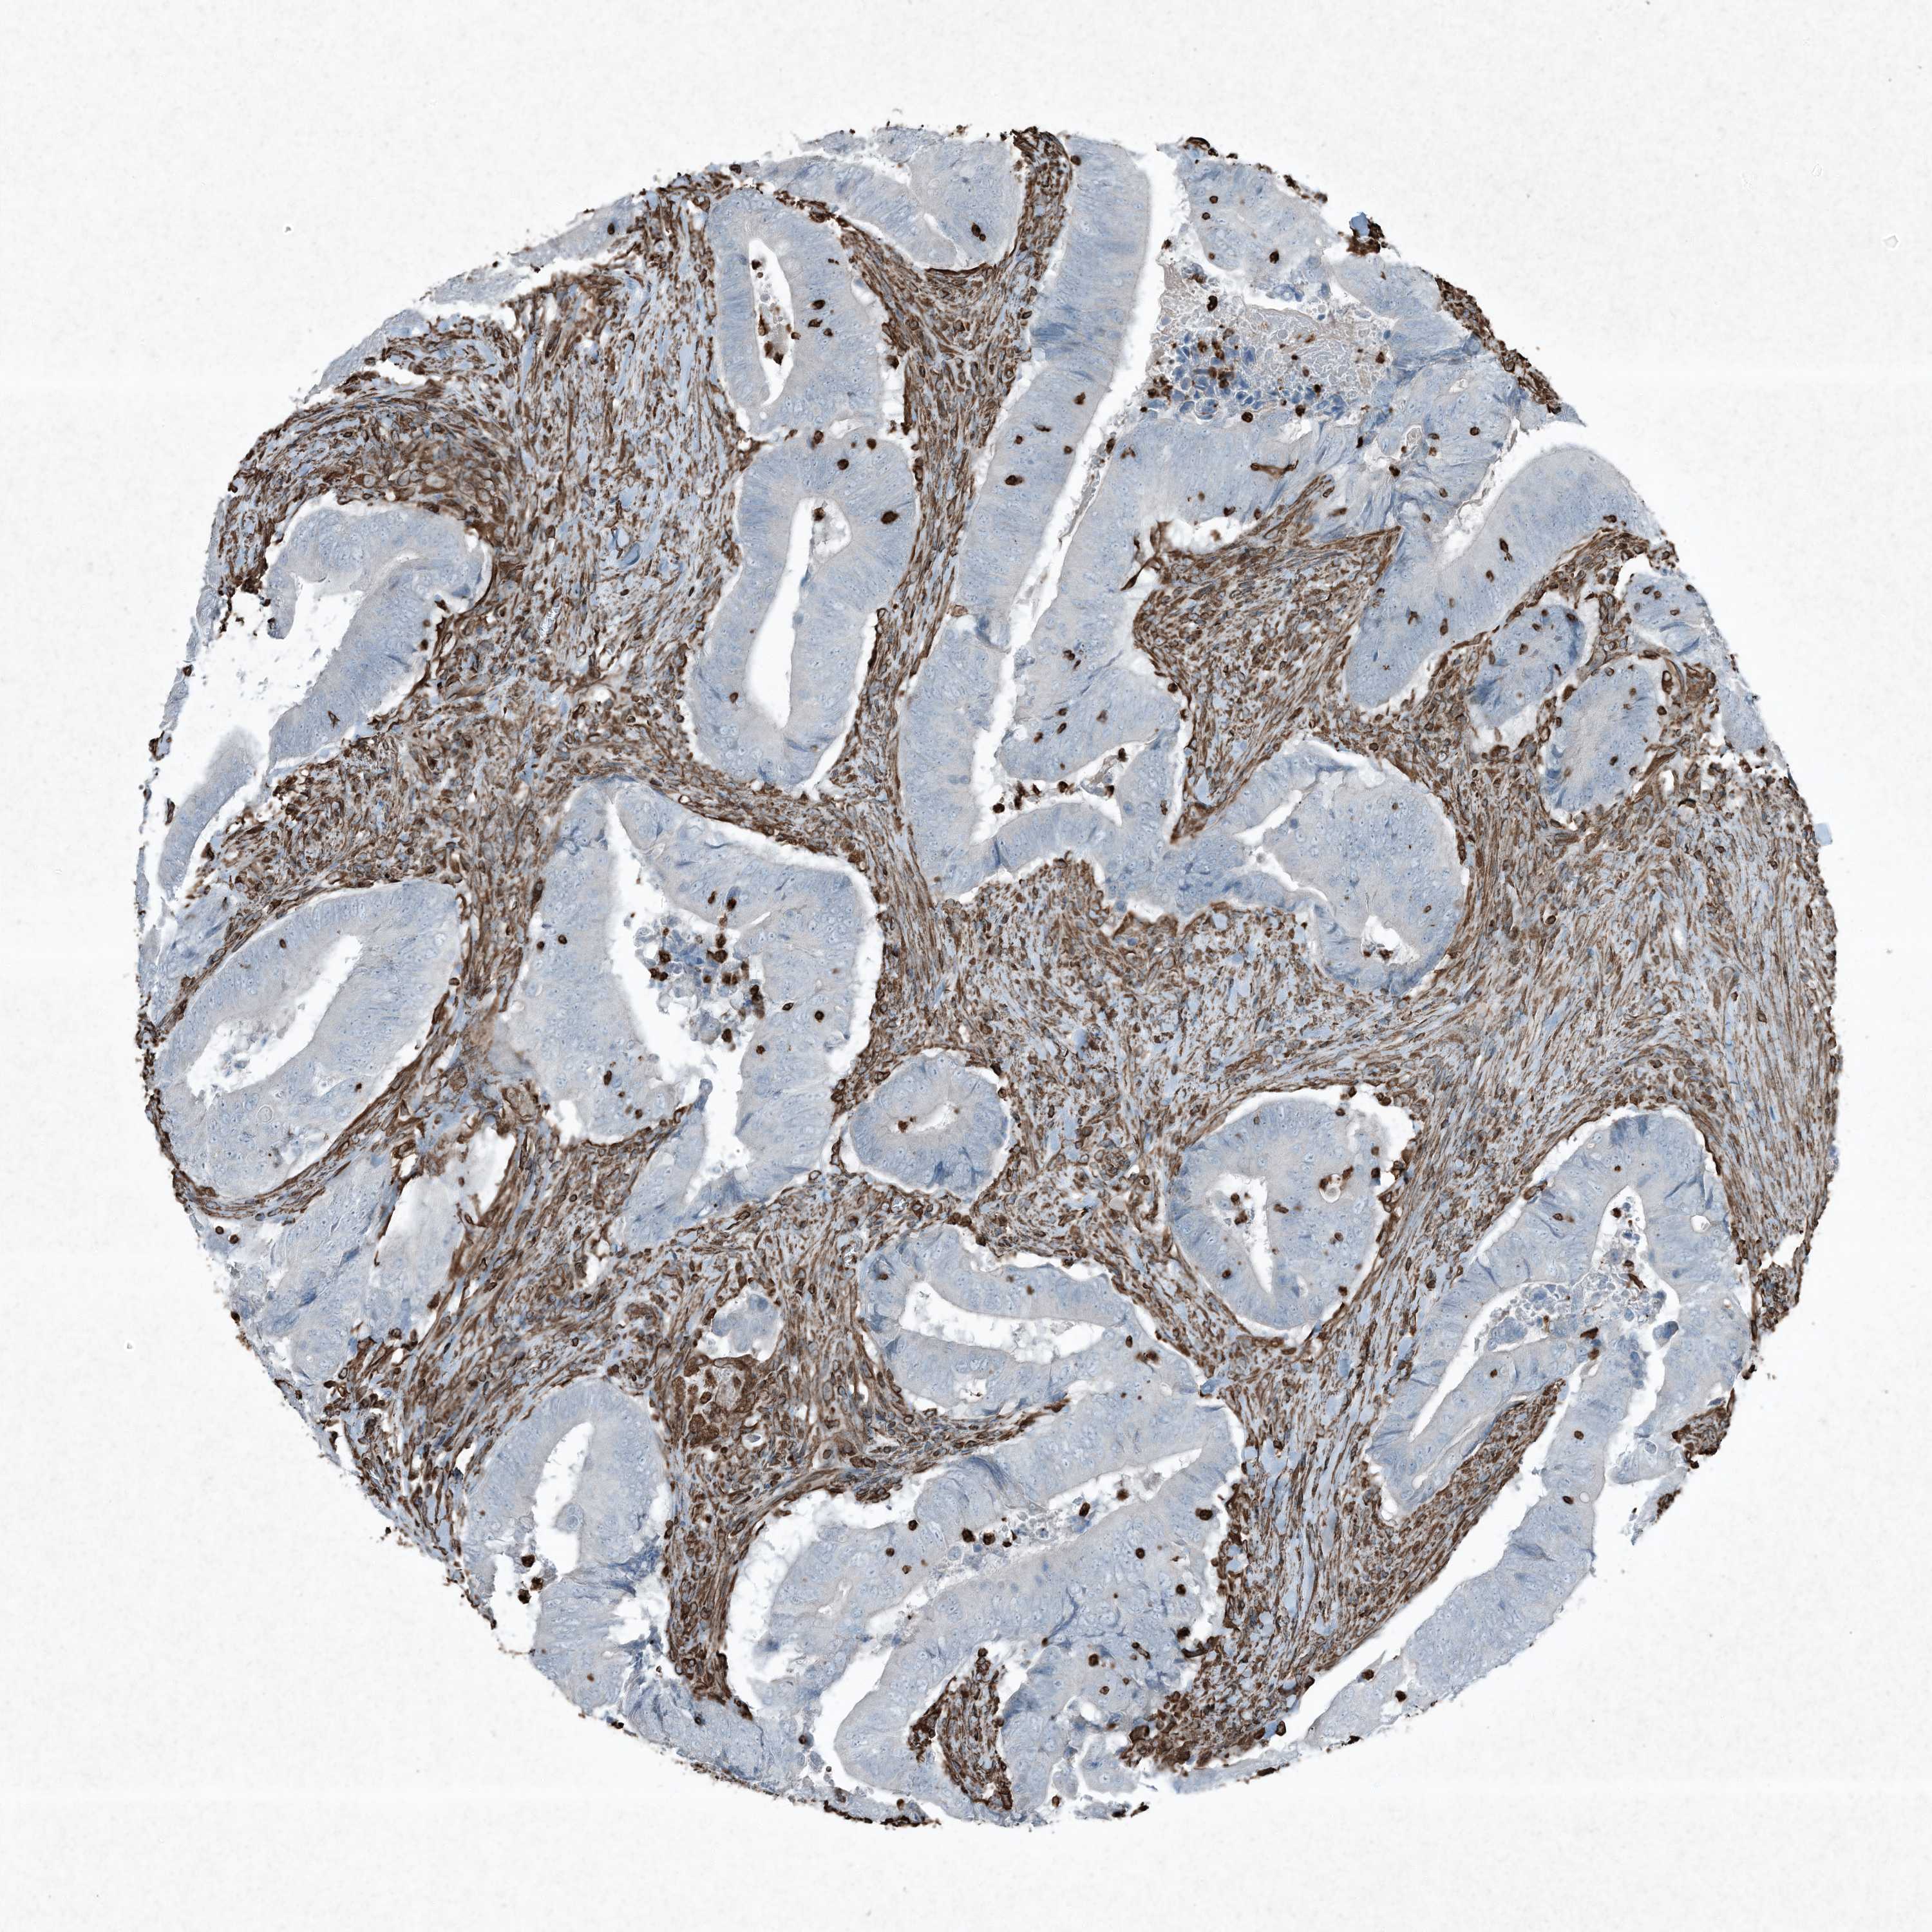

CANCER COLORECTAL CANCER Show tissue menu

COAD TCGA COAD VALIDATION READ TCGA READ VALIDATION PROTEIN COAD CPTAC PROTEIN EXPRESSION

ANTIBODIES

AND

VALIDATION